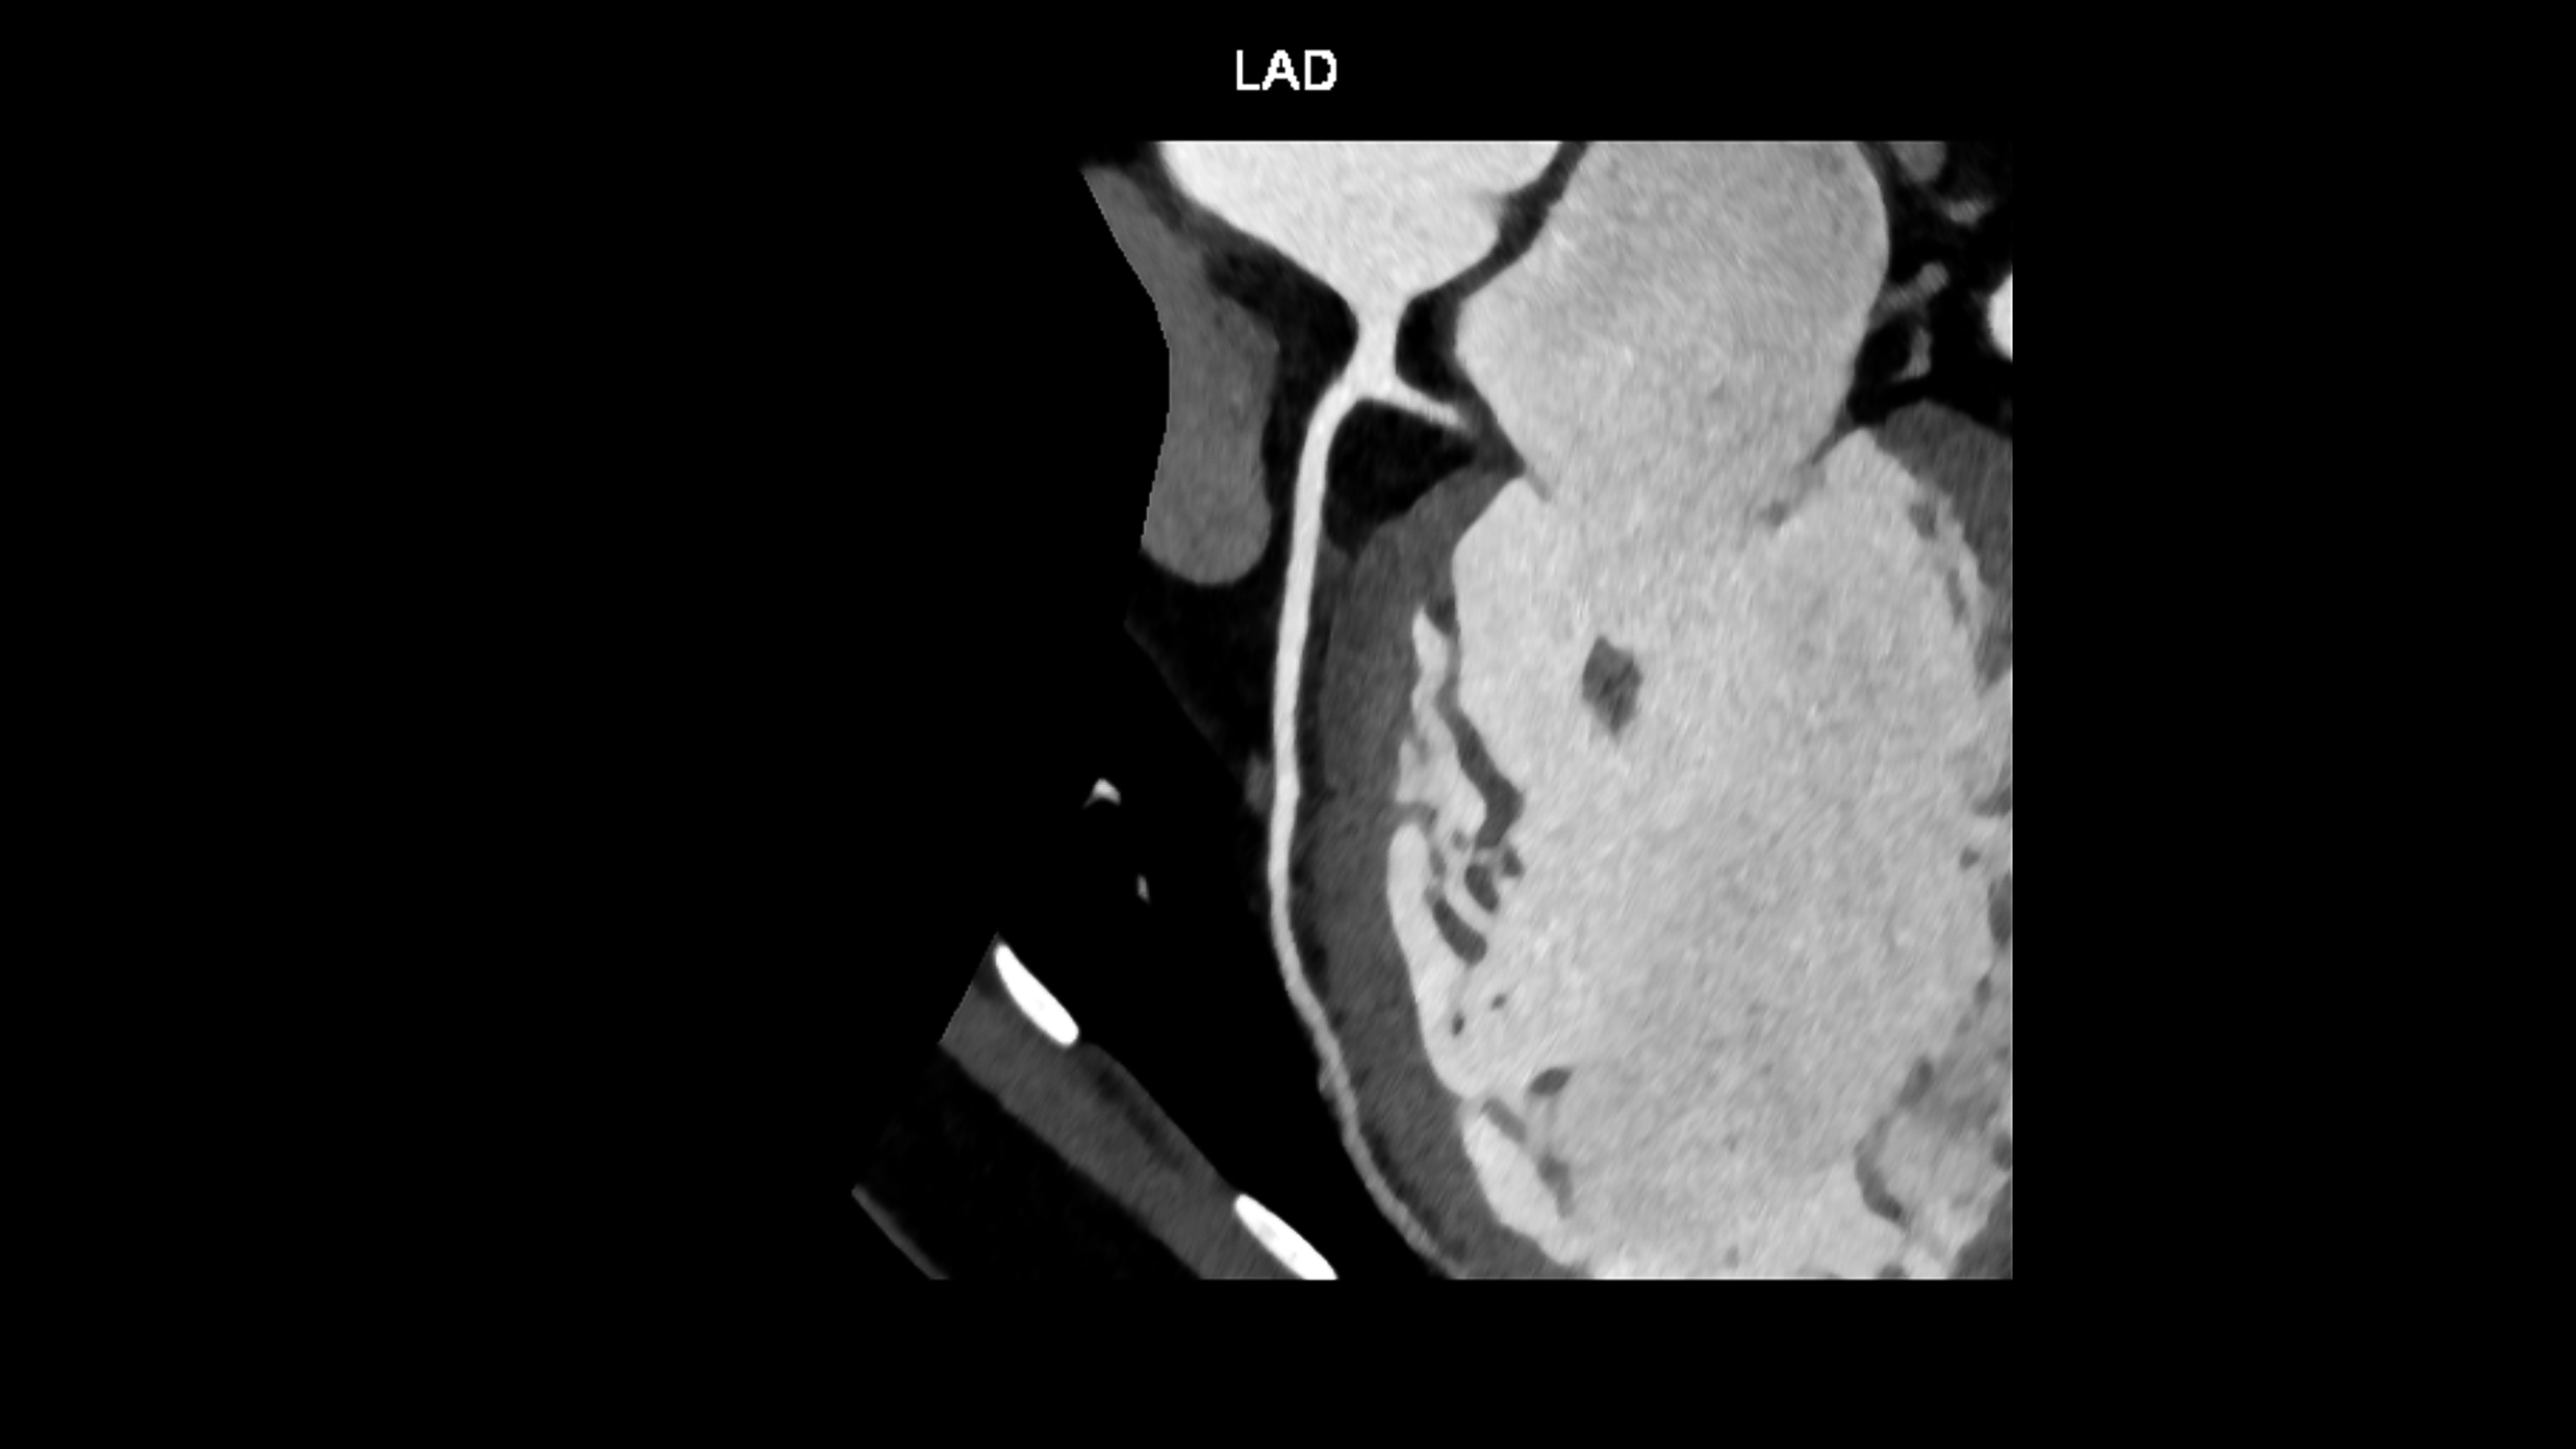

CABG Versus PCI in Multivessel Disease

In a recent study published in The Lancet, it was found that…